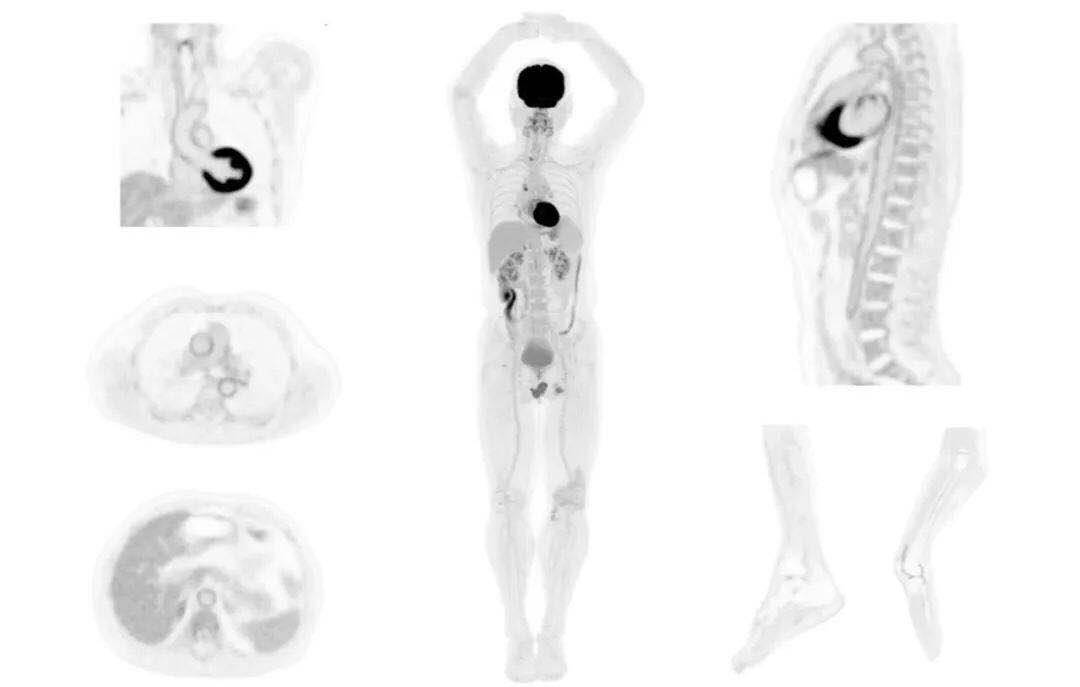

圖例

直腸癌

男,45歲,直腸癌術(shù)后9個(gè)月,發(fā)現(xiàn)肺占位

臨床診斷:直腸區(qū)術(shù)后改變,復(fù)發(fā)伴骶骨受累,雙肺多發(fā)轉(zhuǎn)移

肺癌轉(zhuǎn)移及復(fù)發(fā)

患者男性,66歲,七年前發(fā)現(xiàn)右肺肺癌,其間手術(shù)兩次,共切除兩個(gè)肺葉,復(fù)查;

診斷意見(jiàn),回腸轉(zhuǎn)移,右肺殘留部復(fù)發(fā)